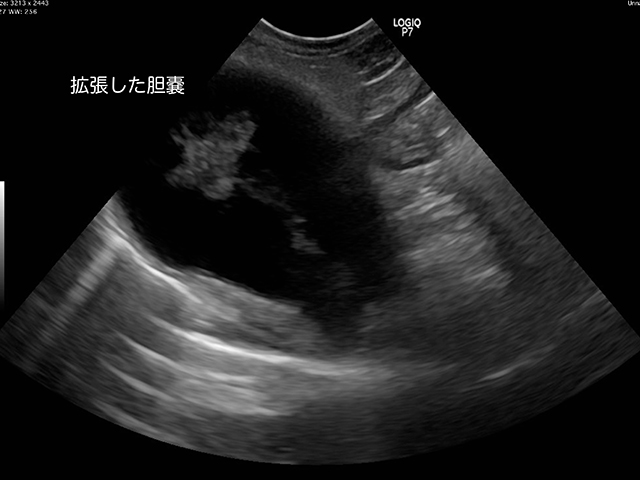

超音波画像診断は、排卵性嚢胞などの単純な嚢胞と、より複雑な嚢胞を区別するために使用されます。複雑な嚢胞は、悪性腫瘍または癌性腫瘍である可能性があります。

一般に、悪性腫瘍には超音波で確認できる内部構造があります。しかし、これらの構造は、必ずしも嚢胞が悪性であることを意味するわけではありません。

超音波スキャンで卵巣の腫瘤が見つかった場合、その腫瘤が良性である可能性が高いか悪性であるかを示すガイドラインがあります。

超音波スキャンで骨盤内に塊と液体が認められる場合は、卵巣嚢腫の破裂が示唆される可能性があります。

嚢胞自体が開いた後に潰れることもあります。しかし、スキャンは決定的なものではないため、医師は診断を下す際に他の要素を考慮します。